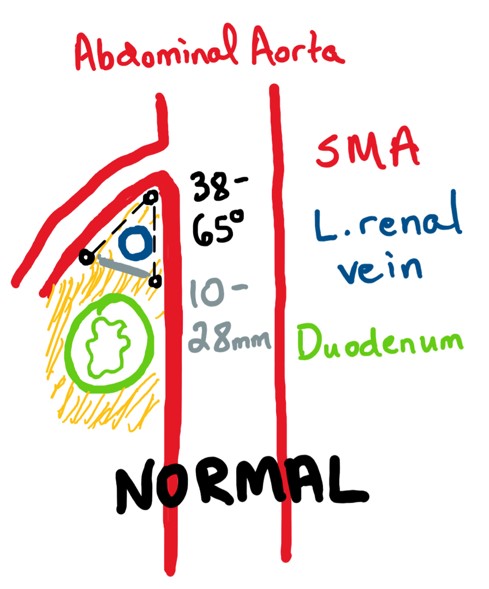

Discussion: SMA syndrome

- Third portion of the duodenum passes between the aorta and the SMA

- Narrowing of the space between the superior mesenteric artery and aorta → compression of duodenum (and often left renal vein) → SBO

- Primarily attributed to loss of the intervening mesenteric fat pad

Drawings courtesy of Allison Auchter, MD, PhD

Discussion: Diagnosis

- Duodenal obstruction with an abrupt cutoff in 3rd portion.

- Aortomesenteric artery angle of ≤25° (most sensitive), particularly if the aortomesenteric distance is ≤8 mm. High fixation of the duodenum by the ligament of Treitz, low origin, or anomalies of the SMA